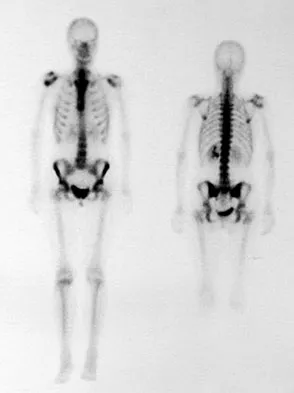

A 73-year-old man reports increasing back and lower extremity pain. A bone scan is shown in Figure 31. What is the most likely diagnosis?

Explanation

The bone scan reveals lesions throughout the skeleton. The patient's age, gender, and pain pattern are consistent with metastatic prostate cancer. Multiple myeloma typically does not have enough osteoblastic activity to produce this bone scan. The patient's age is not consistent with metastatic neuroblastoma (a pediatric disease). Polyostotic fibrous dysplasia may involve multiple active lesions in younger patients but does not have such a widespread distribution of lesions. Hodgkin's lymphoma can involve bone, but the widespread discrete appearance on this bone scan is most consistent with metastatic prostate cancer. In a patient with widespread bone metastases from prostate cancer, bisphosphonates may play a critical role in treatment by decreasing pain and the number of fractures. Roudier MP, Vesselle H, True LD, Higano CS, Ott SM, King SH, Vessella RL: Bone histology at autopsy and matched bone scintigraphy findings in patients with hormone refractory prostate cancer: The effect of bisphosphonate therapy on bone scintigraphy results. Clin Exp Metastasis 2003;20:171-180.